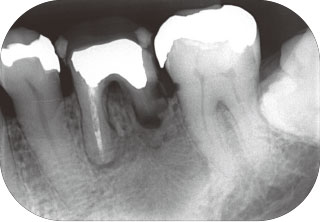

このGPという根管充填材料はなかなかの曲者で、緊密に充填されて、根管壁にへばりついていると除去が難しく、再根管治療で頭を悩ませることの一つになる(図1)。

大まかに除去するのは比較的簡単だが、イスムスや根尖孔付近に付着したものは容易には除去できない。

それ以外にも根管の内部は複雑な凹凸があり陥凹部などに付着した感染源となる起炎物質やGPはファイル操作だけでは取り切れていないのが現状である(図2)。

図1 根管内部は様々なもので汚染されている

図4 初診時レントゲン像

図6 根管治療後1Y後のレントゲン像